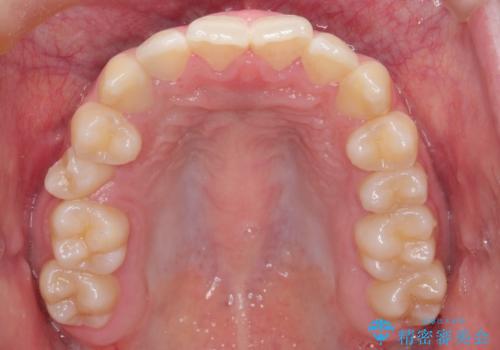

- 右上の小臼歯が大きくねじれており、噛み合わせや見た目に影響を与えている状態でした。診察の結果、インビザライン単独では十分な回転が得られにくいと判断。そのため、基本的な歯列の移動はインビザラインで行いながら、部分的にワイヤー矯正を併用するコンビネーション治療を計画しました。

まず、インビザラインで歯列全体を整えながら、スペースを確保しました。その後、部分ワイヤーを装着し、右上小臼歯の捻転を効率よく改善。ワイヤーの力を活用することで、より確実に歯の向きを整えることができました。治療後は、「しっかり噛めるようになり、見た目も自然になった」と患者様にもご満足いただきました。